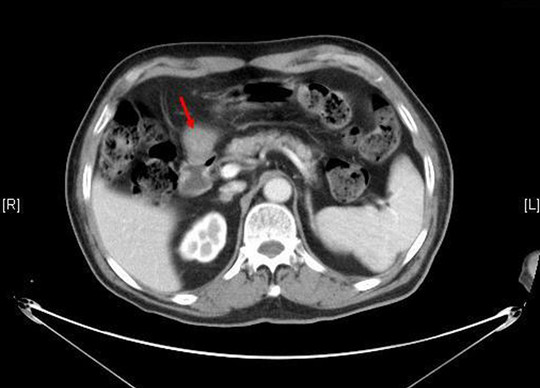

男性患者,80岁,4月底因反复咳嗽5月余,伴气喘一周,渐感胸痛、胸闷和气促等不适,来我院就诊,行胸部动态CT提示气管内肿物:右肺中间段支气管闭塞,见类圆形软组织密度影,边界不清,大小约为4.1*3.6cm,边缘见毛刺征,增强后明显不均匀强化,两肺见斑片影、磨玻璃影;支气管镜检查提示:右肺中叶支气管开口下2cm见软组织肿物、堵塞支气管腔,支气管镜体完全不能通过。入院诊断:右肺恶性肿瘤、心房颤动、脑梗塞后遗症、2型糖尿病、高血压病(极高危)和肾功能不全。经内科对症处理后,临床症状未见缓解。院内会诊和积极术前准备后,拟行纤维支气管镜下肿物活检术和氩等离子电凝切除术。